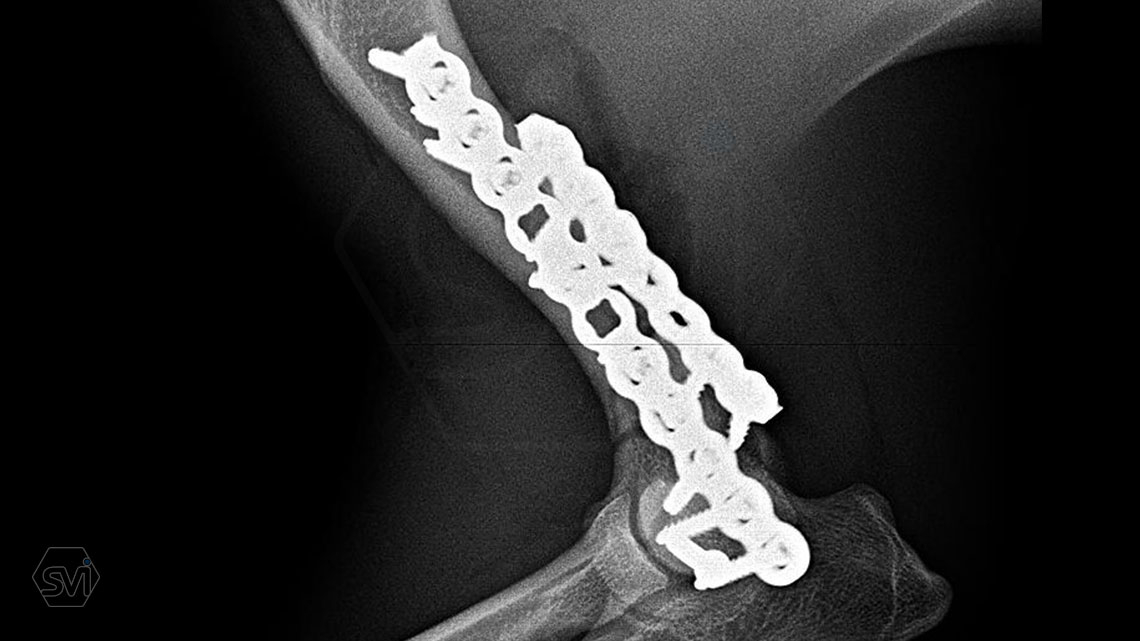

In our first case, we got right to the heart of it: we operated on a 2-year-old dachshund-type mixed dog weighing 9 kg, who overstretched his right humerus while stepping on pallets and suffered a Y-shaped humerus fracture that extended into the elbow joint combined with a large longitudinal splinter. To treat the fracture, we chose the new, cutable poliaxial locking plate, and immediately placed two, one medially and one caudolaterally. The intercondylar fracture and the longitudinal diaphysis fragment were each fixed with a 2.4 lag screw.

The ability to transition between sizes (2.0-2.4) was very useful. We positioned the plate with thinner (2.0 mm) cortical screws, the fragments were fitted to each other, and after the final state was established, we further stabilized the system with the locking screws placed in the empty holes, and then the thinner cortical screws were also replaced with thicker locking ones.

The plate behaved very well, it was much easier to work with than the straight plates used so far, it was easy to cut to size and shape it on the curved dachshund bone.

The advantage of polyaxiality proved to be particularly useful here, where it is very easy to drive the screw into the joint! There is no need to talk about the advantages of lockig systems around the elbows, where the pulling and stretching forces are magnified.

TIP: On the medial side, the very short screw above the fracture line was only used as a "blind plug" so that the hole would not remain without a screw, and the plate would not have a weak point above the fracture.More information: